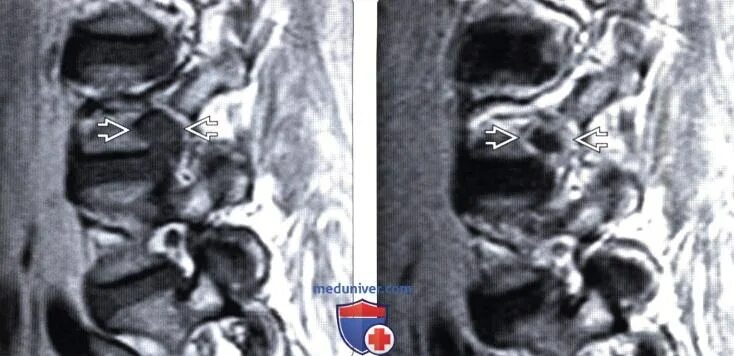

Экструзия l5 s1 диска что это такое